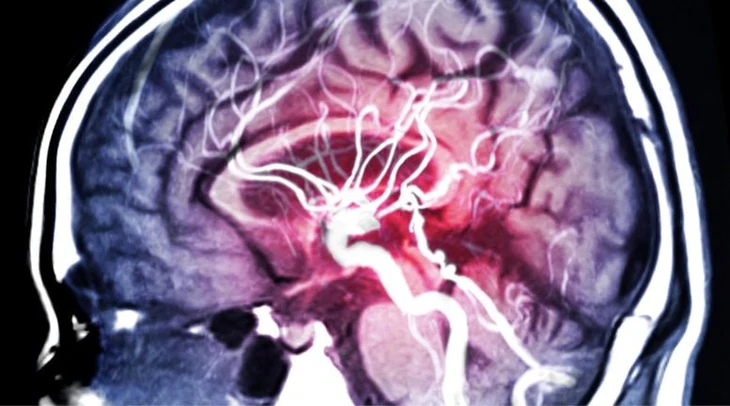

Tăng huyết áp âm thầm tàn phá não bộ trước khi chỉ số huyết áp tăng - Ảnh: Stock

Theo đó, những rối loạn ở tế bào não và mạch máu xảy ra âm thầm trong giai đoạn tiền tăng huyết áp. Những thay đổi này tạo nền tảng cho suy giảm nhận thức về sau, bao gồm suy giảm nhận thức do mạch máu và cả bệnh Alzheimer.

Tế bào nội mô lót mạch máu có biểu hiện lão hóa sớm, chuyển hóa năng lượng thấp hơn và xuất hiện dấu hiệu rò rỉ của hàng rào máu não.

Tế bào thần kinh trung gian mất cân bằng giữa kích thích và ức chế, tương tự mô hình rối loạn ở bệnh Alzheimer. Tế bào ít sợi nhánh, vốn bao bọc sợi trục thần kinh bằng lớp myelin, lại giảm biểu hiện các gene duy trì lớp bảo vệ này. Nếu myelin suy yếu, khả năng truyền tín hiệu giữa các tế bào não cũng suy giảm, ảnh hưởng trực tiếp đến trí nhớ và tư duy.